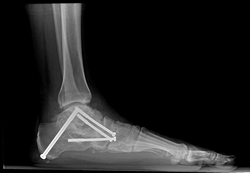

X-ray of a foot as viewed from the side in a patient with a more severe deformity. This patient required fusion of the middle of the foot in addition to a tendon transfer and cut in the heel bone.